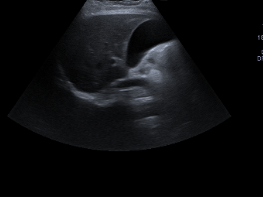

Ecografía abdominal:

Hígado y bazo normales, vesícula alitiásica, riñones normales. Páncreas con porción cefálica engrosada, contornos irregulares y ecogenicidad heterogénea, con áreas hipodensas sugestivas de edema y leve líquido peripancreático. No hay líquido libre intraperitoneal significativo.